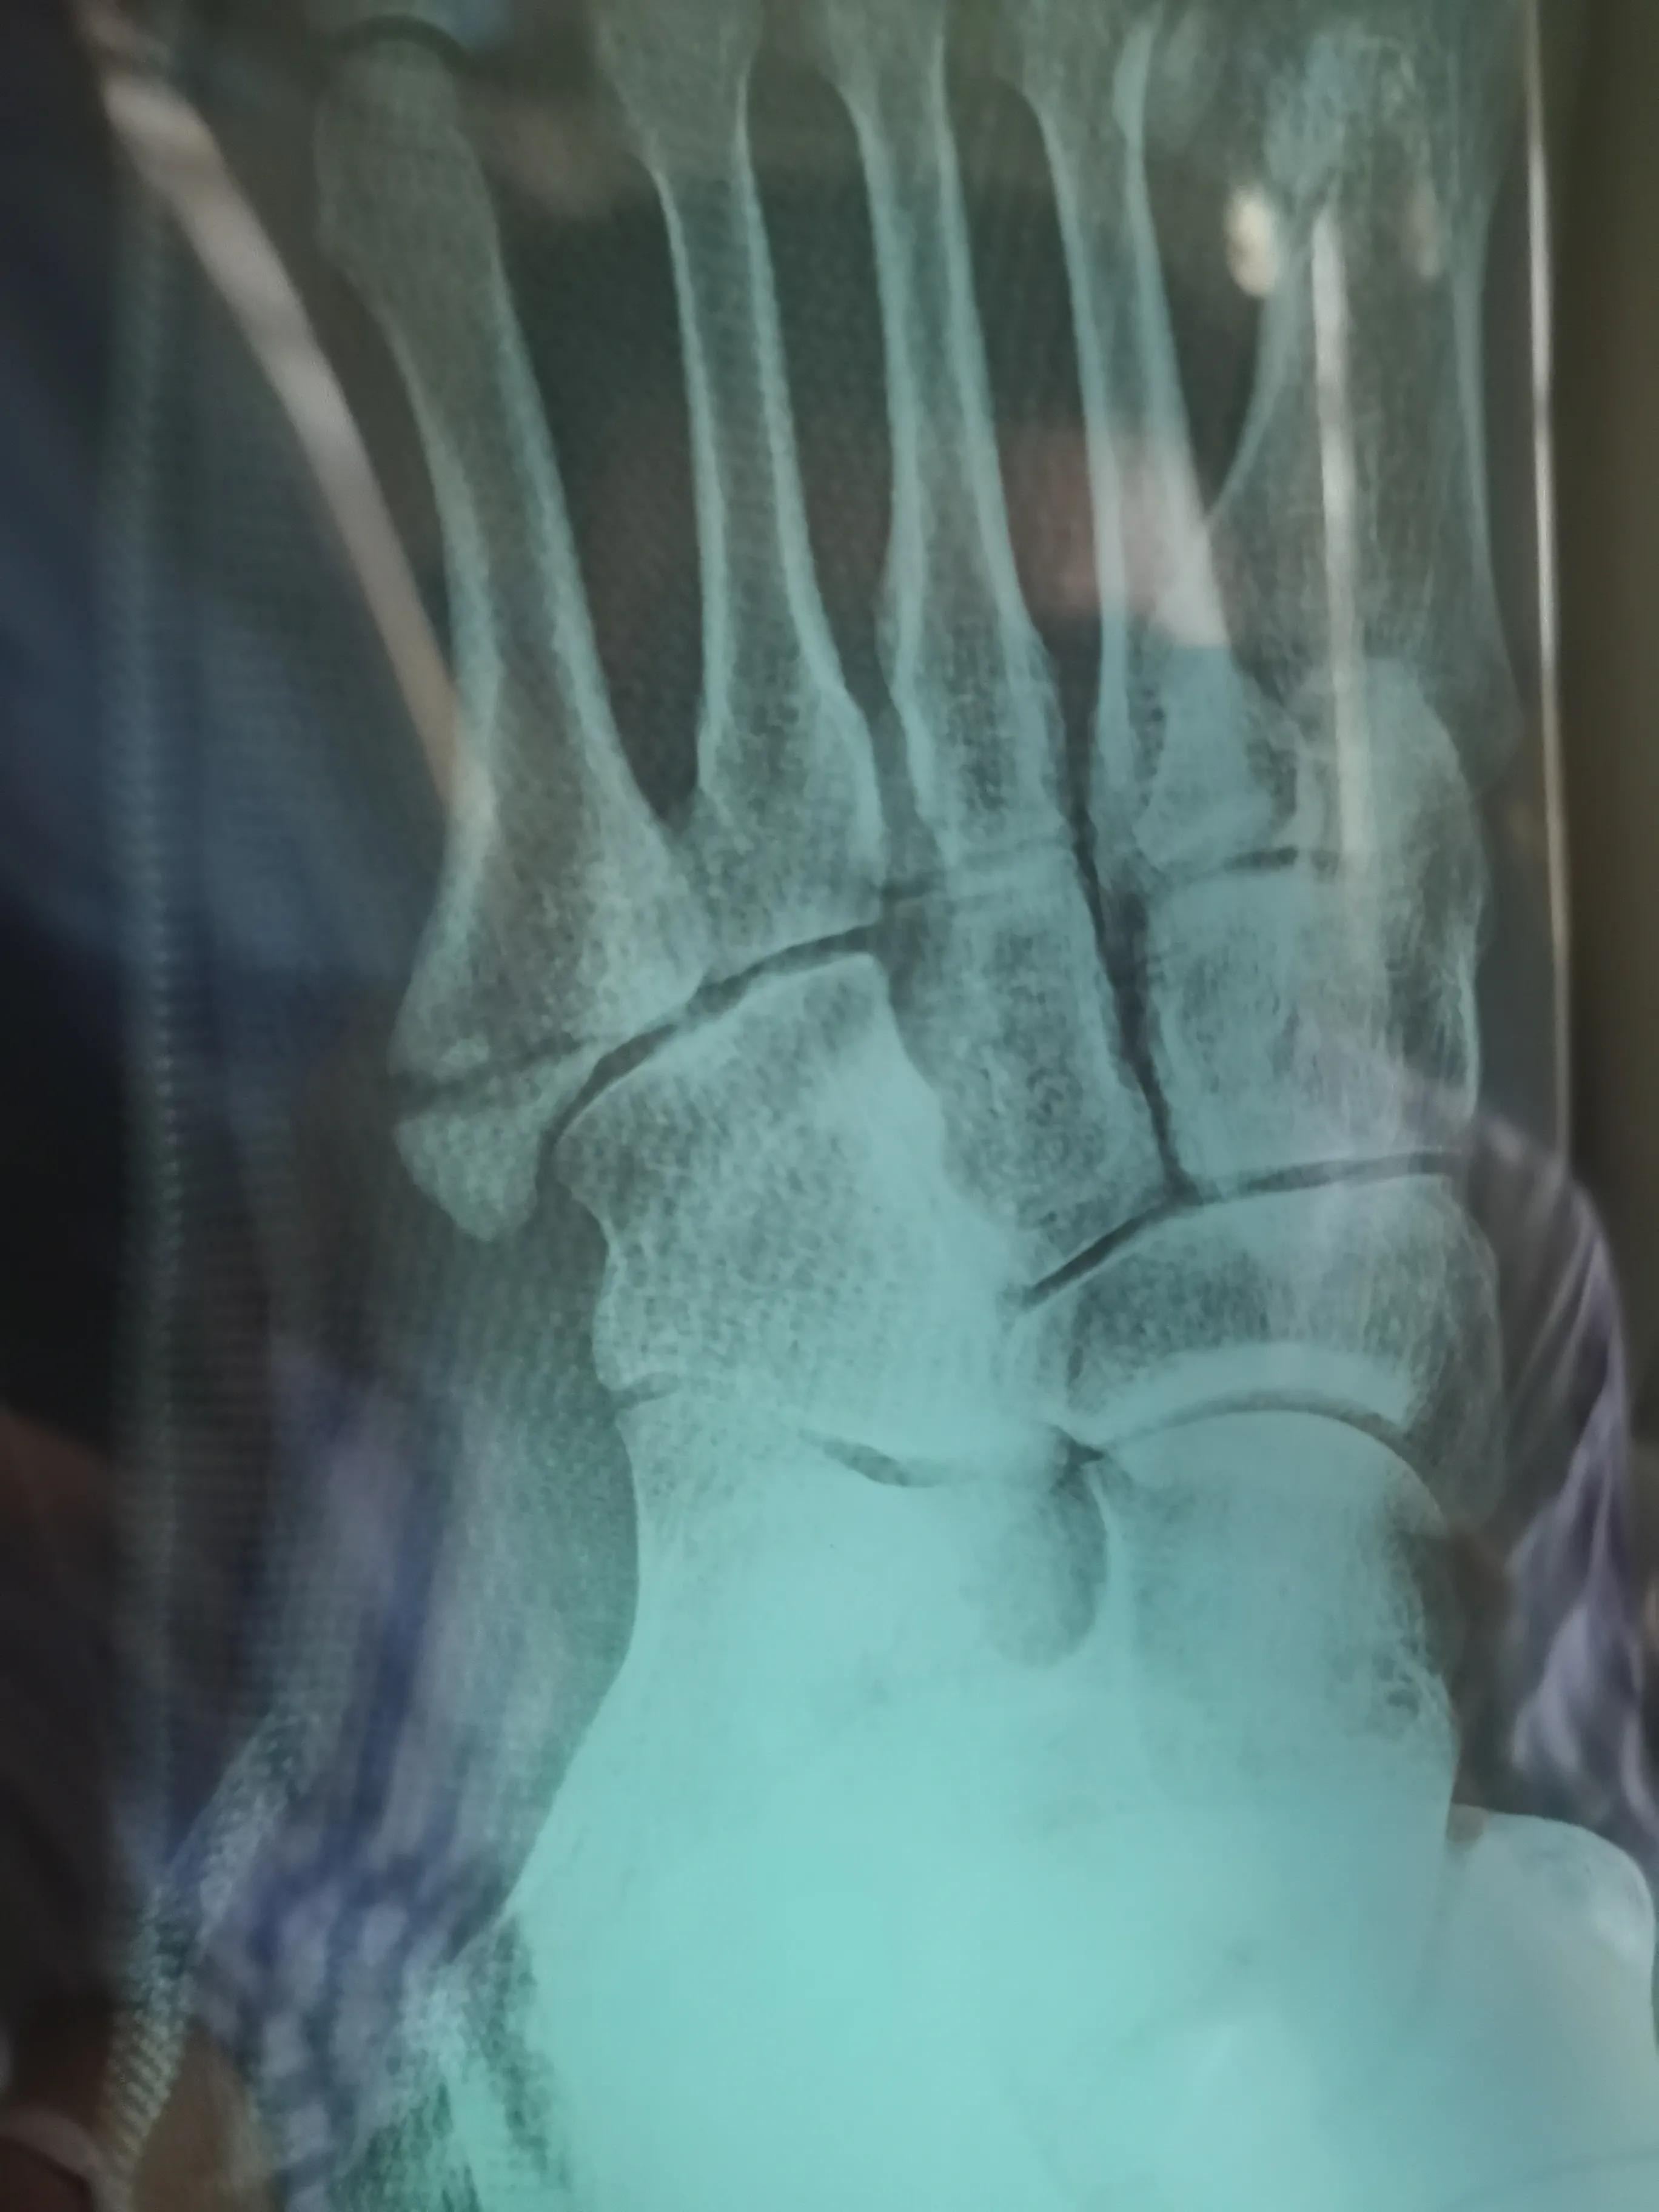

看片子骨缝比较大了,有点移位,而且中间崩碎了一块,一直找不到,后来复查才发现那个碎片掉落在骨缝当中了

此图可以看见中间碎片在骨缝里面